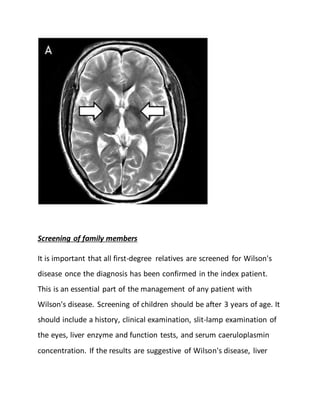

Computer-assisted tomography and magnetic resonance imaging of the

liver do not help in the specific diagnosis of Wilson's disease, although

these imaging techniques will also detect non-specific associations of

Wilson's disease such as splenomegaly and abnormalities in hepatic

parenchyma. Central nervous system imaging with computer-assisted

tomography or MRI demonstrate generalized cerebral atrophy and

abnormalities in the basal ganglia.